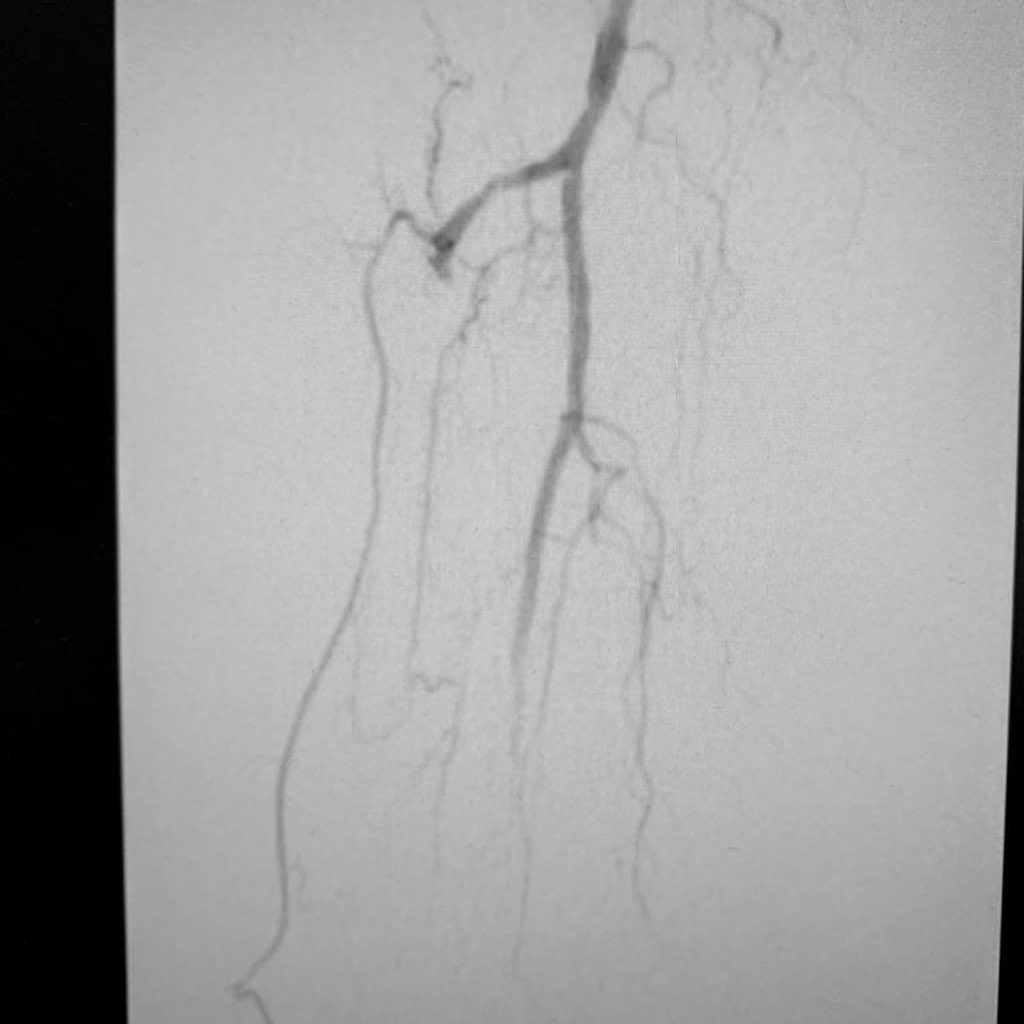

Patient with multiple small arterial ulcers involving the toes 1-3 with poor runoffs. Targeted recanalization of the AT with great flow to the wound. This patient will be plugged into our clinic and watched closely to assess healing.